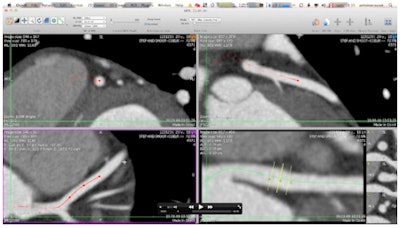

![]() |

| Advanced image analysis tools help radiologists establish more precise, evidence-based diagnoses. In these examples, OsiriX open-source software was used. (Provided by Prof. Osman Ratib) |